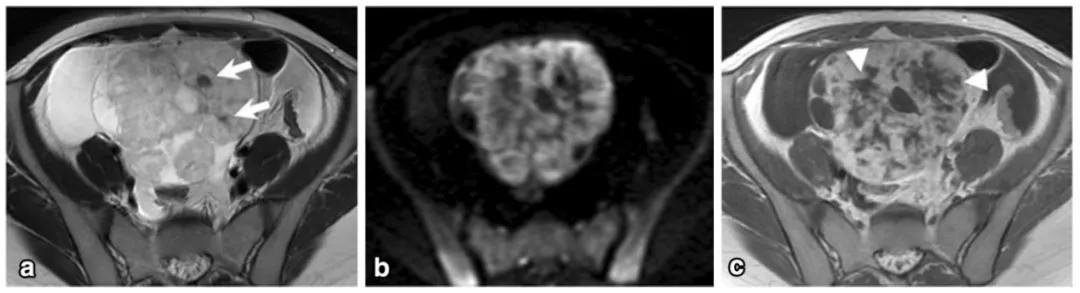

女,12 岁,卵巢 Burkitt 淋巴瘤。双侧卵巢肿物,T2WI 信号稍高(图 a),DWI 呈高信号(图 b),增强扫描明显强化(图 c),箭头显示肿物边缘多发囊性结节,为卵泡保留征。